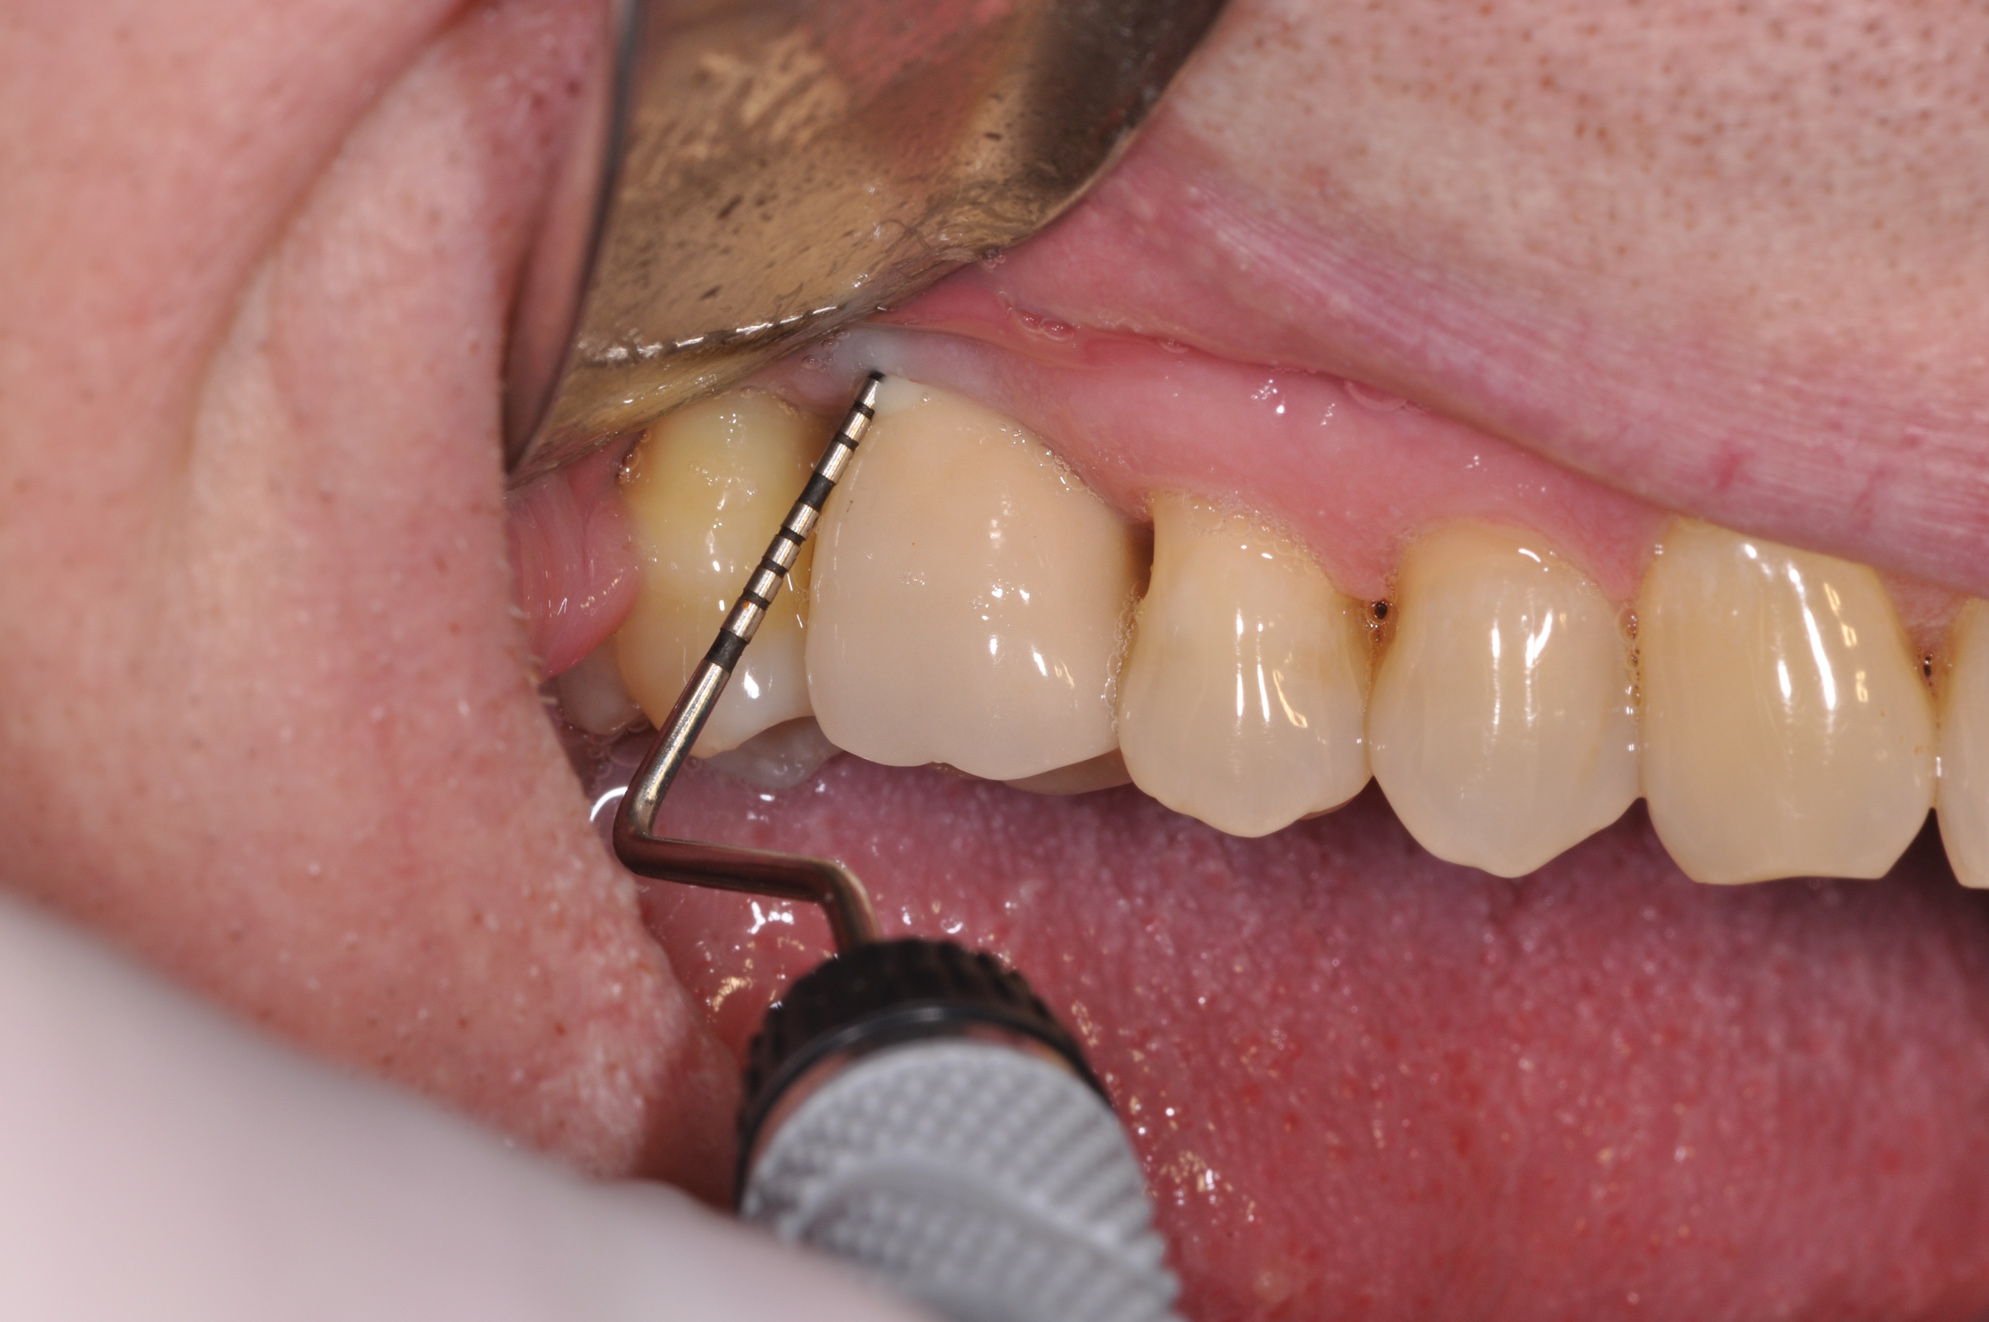

The clinician should review and reinforce with the patient the patient-administered oral hygiene efforts. Use of an intraoral stain to demonstrate inadequate plaque control has been shown to be effective in patient motivation.19 Nonsurgical peri-implant treatment should consist of mechanical removal of the bacterial biofilms and elimination or control of all local plaque retentive factors. Curettes, sonic and ultrasonic instruments, as well as air polishing with glycine powder are all effective methods of biofilm removal.20 The use of local antibacterials and local or systemic antibiotics appear to have minimal benefit.21 Once the treatment of peri-implant mucositis has been rendered, it is very important that the oral healthcare provider evaluate the response to therapy (Figure 3 and Figure 4). If initial therapy fails to resolve the peri-implant inflammation, it may be beneficial to assess the marginal fit and design of the implant prosthesis with regard to patient access, as well as the possible presence of cement remnants.

Fig 4. Four weeks after treatment, the patient presented with healthy peri-implant tissues.

Figure 4